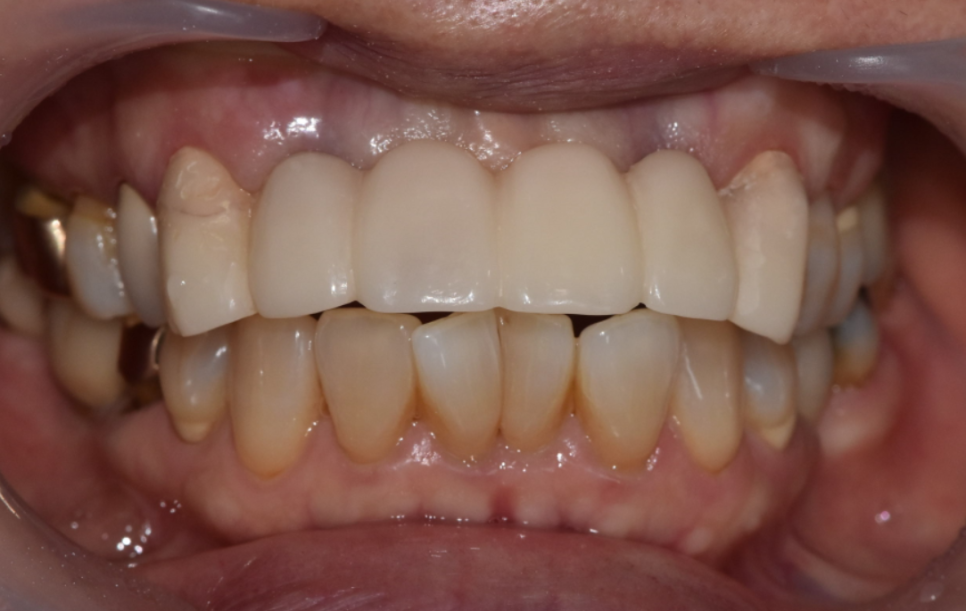

그렇게 완성된 최종 브릿지.

240719

옆 치아와의 색도 자연스럽게 나왔고,

모양과 크기도 적절했습니다.

무엇보다 환자분께서 정말 마음에 들어 하셨어요.

브릿지 교체는 단순히 낡은 것을 새것으로 바꾸는 단순한 작업이 아닙니다.

기존 치아 상태, 뼈 상태, 교합 상태까지 종합적으로 판단해야 합니다.